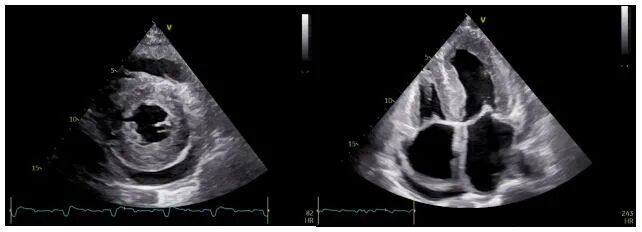

随后,该患者前往厦心就诊,通过心电图,心脏磁共振、心脏超声心肌应变力检测等检查,需要考虑的可能性诊断:浸润性心肌病。其中,最常见的是心肌淀粉样变性(Amyloid cardiomyopathy, CA)。经过一系列的血液和影像学检查,病人诊断为甲状腺素运载蛋白淀粉样心肌病(transthyretin amyloid cardiomyopathy, ATTR-CA)。当看到典型的心电图低电压和原因不明的心肌肥厚的超声改变,应该高度怀疑淀粉样心肌病。医生高度怀疑为“心肌淀粉样变”。

心脏超声显示肥厚的心室壁和室间隔

心超心肌应变力检查提示心尖应变力保留这是诊断心肌淀粉样变的超声特异性改变